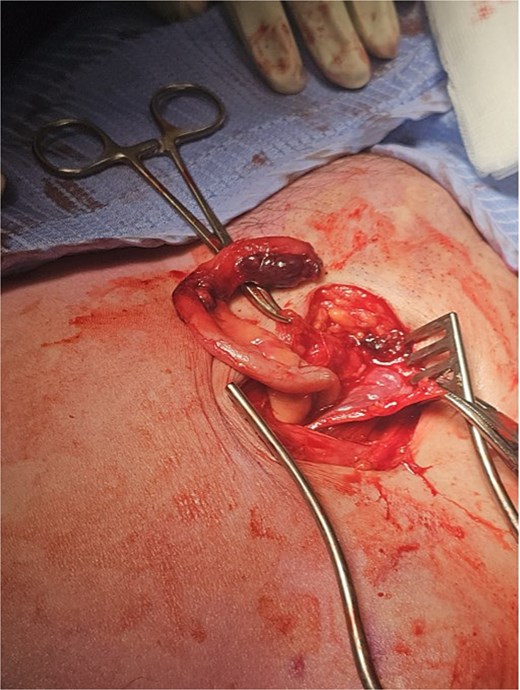

The working radiological diagnosis was an incarcerated Amyand’s hernia. However on examination, the lump appeared to be below the inguinal ligament more in keeping with a femoral hernia. Therefore under general anaesthesia, a high approach was taken. This revealed a femoral hernia under the inguinal ligament. Rectus sheath was opened transversely. A preperitoneal reduction was unsuccessful so peritoneum was opened in the right iliac fossa. This revealed an appendix incarcerated in the femoral hernia. The hernia was reduced revealing a grossly inflamed appendiceal tip (Fig. 3). An open appendicectomy was done, the hernia was closed with an intraperitoneal 1–0 Ethibond suture before closing the peritoneum, fascia, and skin.